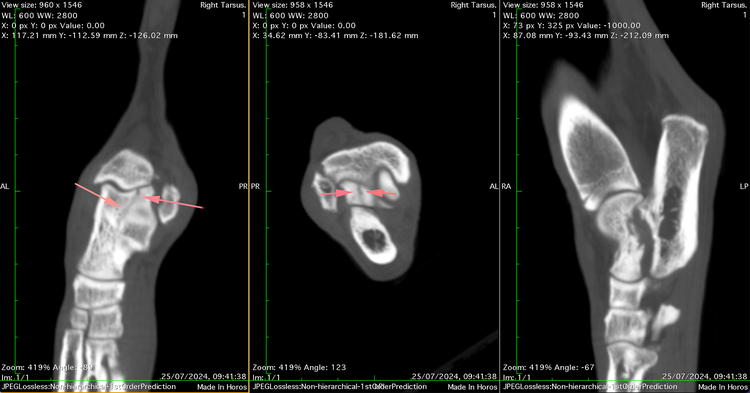

Specialist Orthopaedic surgeon Mark Bush took charge of the case and immediately identified a swollen and painful tarsus. CT imaging uncovered rare and complex fractures - one affecting the sustentaculum tali of the calcaneus and another involving the lateral ridge of the talus, extending into the joint.

Due to their unusual, non-displaced nature and challenging location, initial treatment was conservative. Lola’s limb was immobilised in a cast for six weeks with regular bandage changes. On re-examination, the calcaneal fracture was showing signs of healing; however, the talar fracture remained unchanged and Lola was still lame.

Instead, Mark and the team opted for an innovative solution: a headless compression screw (HCS), commonly used in human orthopaedic surgery for peri-articular fractures. The HCS generates compression along the fracture line thanks to its differential thread pitch, while its headless design allows full burial within the bone - eliminating the risk of joint interference.

Postoperatively, Lola’s limb was supported in a bandage for an additional six weeks to protect the repair. At recheck, CT scans confirmed good healing progress, and the bandage was removed. Just two weeks later, Lola had returned to full activity, completely sound and free from lameness.